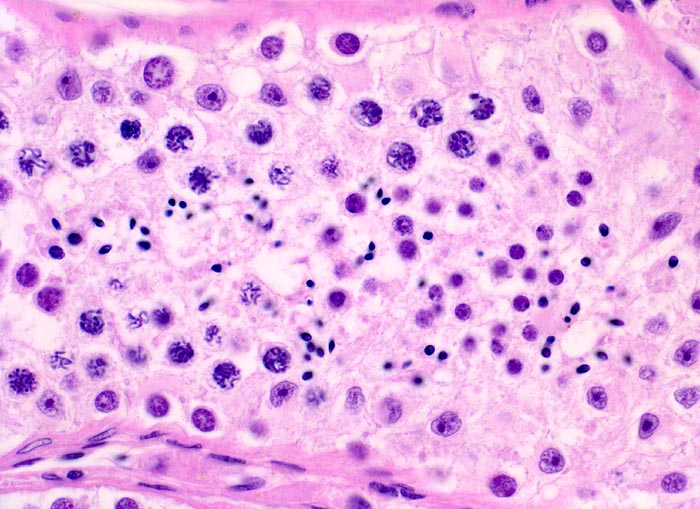

Makroskopisch imponieren Seminome als gut begrenzte weiche crèmefarbene Knoten oder diffuses Intiltrat. Mikroskopisch findet sich eine uniforme Population grosser Zellen mit prominentem zentralem Nukleolus, welche durch schmale Bindegewebssepten voneinander getrennte Nester bilden. Ein leukozytäres Entzündungsinfiltrat, synzytiotrophoblastäre Riesenzellen und Mikroverkalkungen können zusätzlich vorhanden sein. Gelegentlich induziert der Tumor eine ausgeprägte granulomatöse Entzündung. Dies kann zur Fehldiganose einer granulomatösen Orchitis führen.

• Scharf begrenzter Tumorknoten mit eosinophilen Nekrosearealen.

• Unterschiedlich breite solide Tumorzellstränge aus monomorphen Zellen mit grossen hyperchromatischen Kernen und einem solitären zentralen prominenten Nukleolus. Reichlich helles Zytoplasma mit scharfen Zellgrenzen.

• Schmale bindegewebige Septen mit Kapillaren und lymphoplasmazellulärem Entzündungsinfiltrat.

• Tubuläre Atrophie des angrenzenden Hodenparenchyms. Einige Hodentubuli enthalten stark atypische pleomorphe Keimzellen (Keimzellneoplasie in situ).